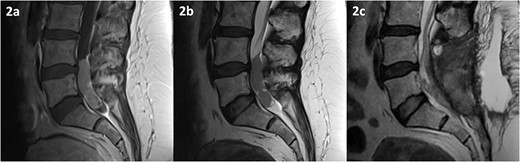

MRI of the spine revealed an intradural lesion between L4-S2, occupying the thecal sac in its entirety, with motor and sensory rootlets being either displaced or encased by the tumour (Fig. 2). The lesion demonstrated heterogeneous enhancement on administration of gadolinium. The differential diagnosis included a primary tumour such as an ependymoma, a potential drop metastasis from the cranial oligodendroglioma, or a metastasis from an unknown primary.

MRI of the spine depicting an intradural lesion between L4-S1. T1-weighted imaging (a) shows heterogeneous enhancement of the lesion upon administration of gadolinium. The lesion is hypointense on T2-weighted imaging (b). Postoperative T2-weighted imaging (c) reveals a small amount of residual tumour.